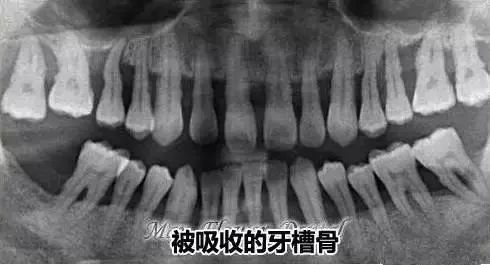

可以看到牙周情况吗?

答:一般是可以的,通常来说,牙齿周围是被牙龈包裹没有很大缝隙的,如果口腔全景片上显示如下面这样的。

牙齿之间缝隙大而且是黑色阴影,牙齿整体比较长,多半是有牙周炎,牙槽骨情况也不好。(如下图)

曲面断层片怎么看科普知识:你会看牙片嘛?今天手把手教你看!_https://www.jmylbn.com_新闻资讯_第16张

被吸收的牙槽骨